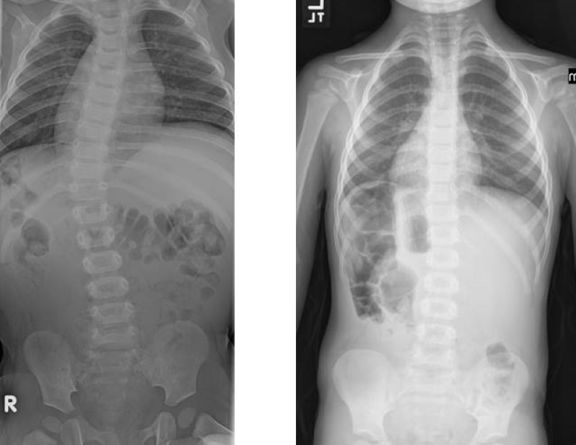

Scoliosis

Emily's spine curvature has continued to increase as she's grown. Now that she's a candidate for spinal fusion surgery, she and her father, Mark, feel it's the right time for surgery to improve her quality of life.

When Jessica's spine curvature began rapidly increasing, she and her parents, Debbie and Doug, knew spine surgery was inevitable. Now that she's completed surgery and recovery, she stands taller and feels stronger than ever before.

Kids who have a spine curvature of more than 40 degrees may benefit from spinal fusion surgery. Here, Jessica and her family share how they coped with spine surgery.